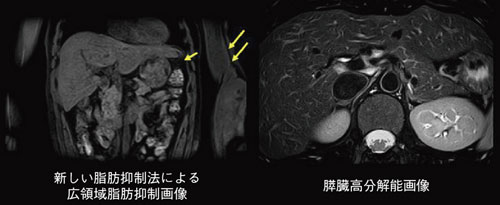

息止め撮像のパフォーマンス向上のために,フェイズエンコード方向とスライス方向のSPEEDERを同時に使用し,より高分解能で,より短時間の息止め検査を可能にする。新しい脂肪抑制技術によって,磁場不均一が発生しやすい胃や脾臓の周辺,また腕と躯幹部の間でも,より高いレベルの脂肪抑制効果を得ることができる。また,呼吸性の細かな動きのアーチファクトを低減することで,ルーチン画像の安定化のみならず,膵臓など各臓器の局所高分解能撮像の実現をめざしている(図3)。

図3 新しいアプリケーション |